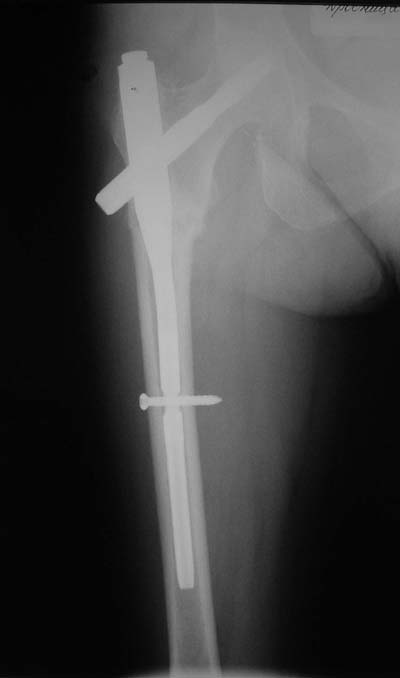

Да? Качество рентгенограмм конечно неочень, но ведь это нестабильный перелом 31.А2.2, не так ли?

Не думаю так. см вложение.

> Да? Качество рентгенограмм конечно неочень, но ведь это

> нестабильный перелом 31.А2.2, не так ли?

Ну, после помещения туда такого гвоздя даже без дистального винта заметной нестабильности уже не остается ;-)

> Не думаю так. см вложение.

Для такого перелома вполне может быть использован диафизарный штифт, который отечественного производства я даже боюсь считать во сколько раз дешевле... Недавно несколько примеров я закидывал.